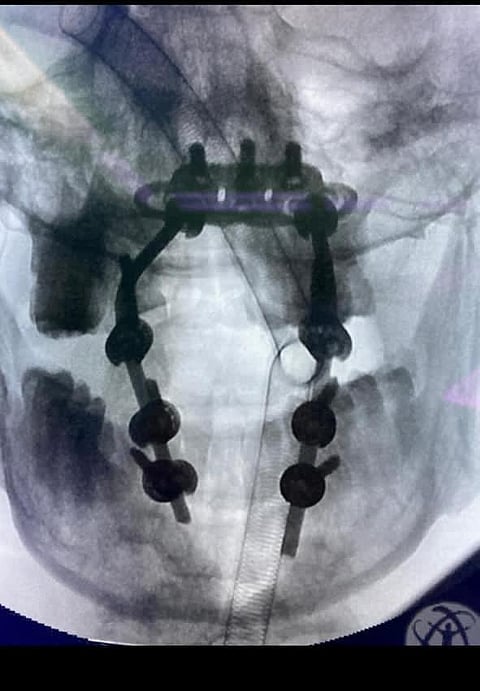

وبيّنت صحة بيشة أن الفريق الطبي المختص قام بإجراء عملية جراحية لإزالة الضغط على الحبل الشوكي وتثبيت الفقرات وإرجاعها لوضعها الطبيعي وتثبيتها بمسامير وقضبان طبية ما بين الجمجمة والفقرة الثالثة العنقية.